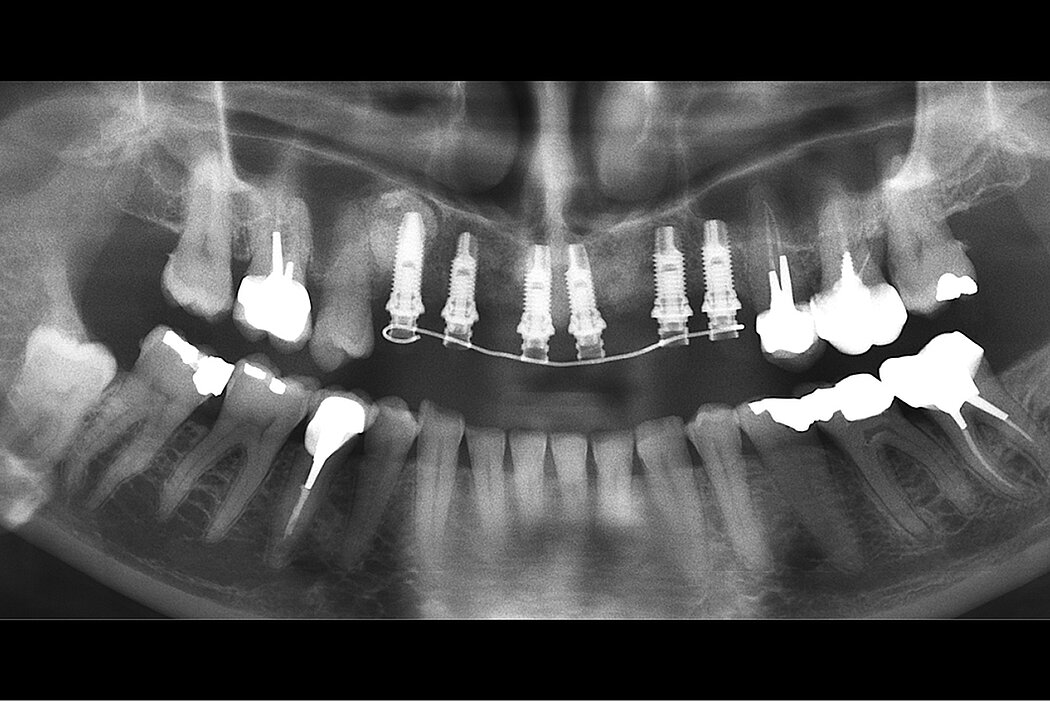

20年随访的侧壁开窗上颌窦底提升

一位62岁的女性健康患者被转诊至Schwartz-Arad手术中心,以拔除右上颌第一磨牙。该临床病例于1997年诊治,随访时间20年。右上颌磨牙区由于牙周缺损,右侧上颌第一磨牙无法治疗。第一和第二右上颌前磨牙缺失。现有的桥体覆盖右上颌尖牙和第一磨牙。由于右上颌窦气化和牙周病变,可用的牙槽嵴不足以植入种植体。患者前来接受治疗以获得固定修复体修复。临床挑战是通过窦底提升手术重建垂直维度的牙槽嵴骨量的同时,在拔牙时进行牙槽嵴保存,以进行第二阶段的种植体植入。

- 使用Geistlich Bio-Oss®和Geistlich Bio-Gide®进行上颌窦底提升获取长期的临床成功。

- 20年随访可见完美修复情况。

口。这时,将窦膜从窦底和内侧窦壁小心地抬起。采用Geistlich Bio-Gide®修复穿孔。由于无法获得种植体初期稳定性,5个月后进行第二阶段,延期植入种植体。上颌窦腔室用Geistlich Bio-Oss®进行骨增量。上颌窦开窗侧壁用Geistlich Bio-Gide®覆盖,粘骨膜瓣复位后用3/0 Vicryl缝合。

该病例随访20年,是Schwartz-Arad手术中心采用Geistlich Bio-Oss®治疗的许多牙槽嵴骨量不足患者中的一例。长期来讲,上颌窦底提升手术中使用Geistlich Bio-Oss®和Geistlich Bio-Gide®进行骨增量是可预测的治疗方法。此外,如果使用Geistlich

Bio-Gide®进行修补上颌窦膜穿孔,不会对种植体植入造成不利影响。